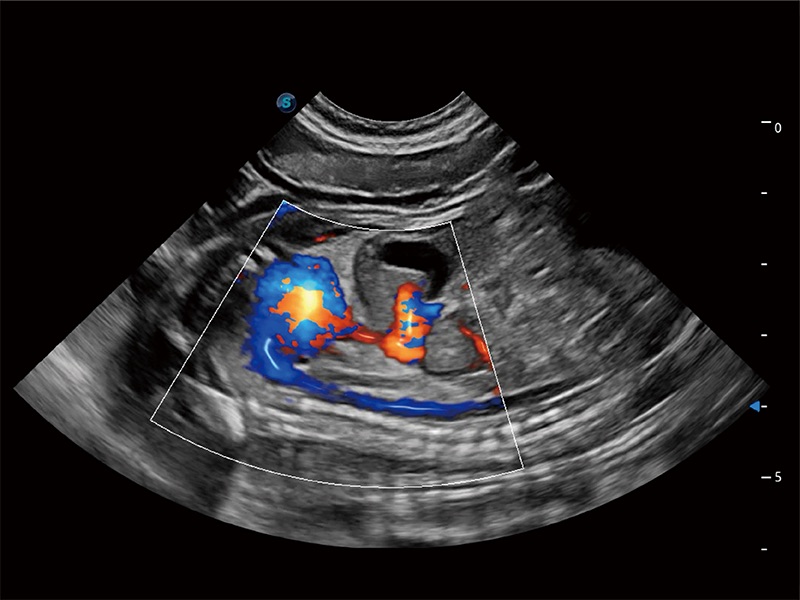

ProPet 80 配备了丰富的心脏探头群、先进的成像技术和专业的心脏测量工具,可帮助动物医生为不同体型和生理结构的动物提供心脏和心肌功能的全面评估。

实时用颜色表示心肌组织运动,观察和定量组织的运动情況,对快速检测与评估心肌的灌注和活性、电传导及心肌收缩和舒张功能等均能提供重要的诊断信息。

通过心肌识别技术与二维斑点追踪技术相结合,对心脏的超声图像进行量化分析。计算心肌17个节段的应变、应变率、速度、位移等,并通过牛眼图的形式进行呈现。

通过360度任意调节3条M型取样线,在同一心动周期上观察心脏不同位置的运动曲线,得到准确的心功能测量数据,有效评估心肌运动及左心室功能。